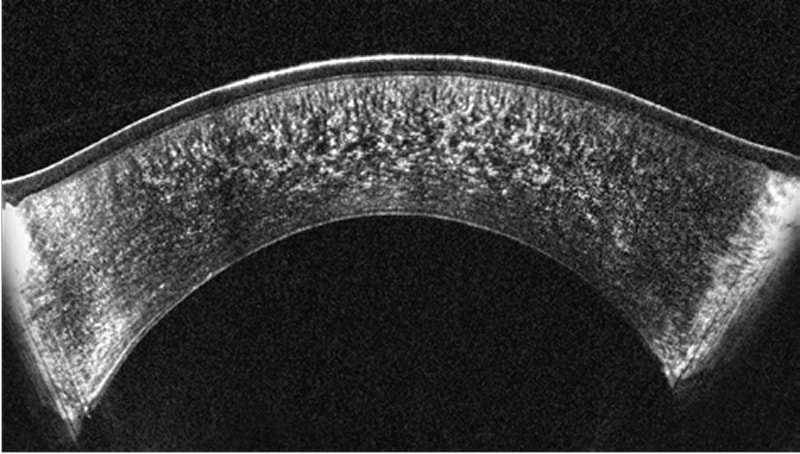

Pentacam® Cornea OCT は、独自のペリセントリックスキャン技術を搭載したスペクトラルドメインOCT方式を採用し、角膜構造の描出において、縦方向分解能1.9μmの画像を提供します。一方Swept Source OCTは、深部まで検査可能ですが、分解能は約10μm前後と性能に差があります。

Corneal Zoomモードは一枚の画像に角膜全体を包括的に描出します。

アベレージングモードは、複数の画像を統合することでより鮮明な画像を生成します。